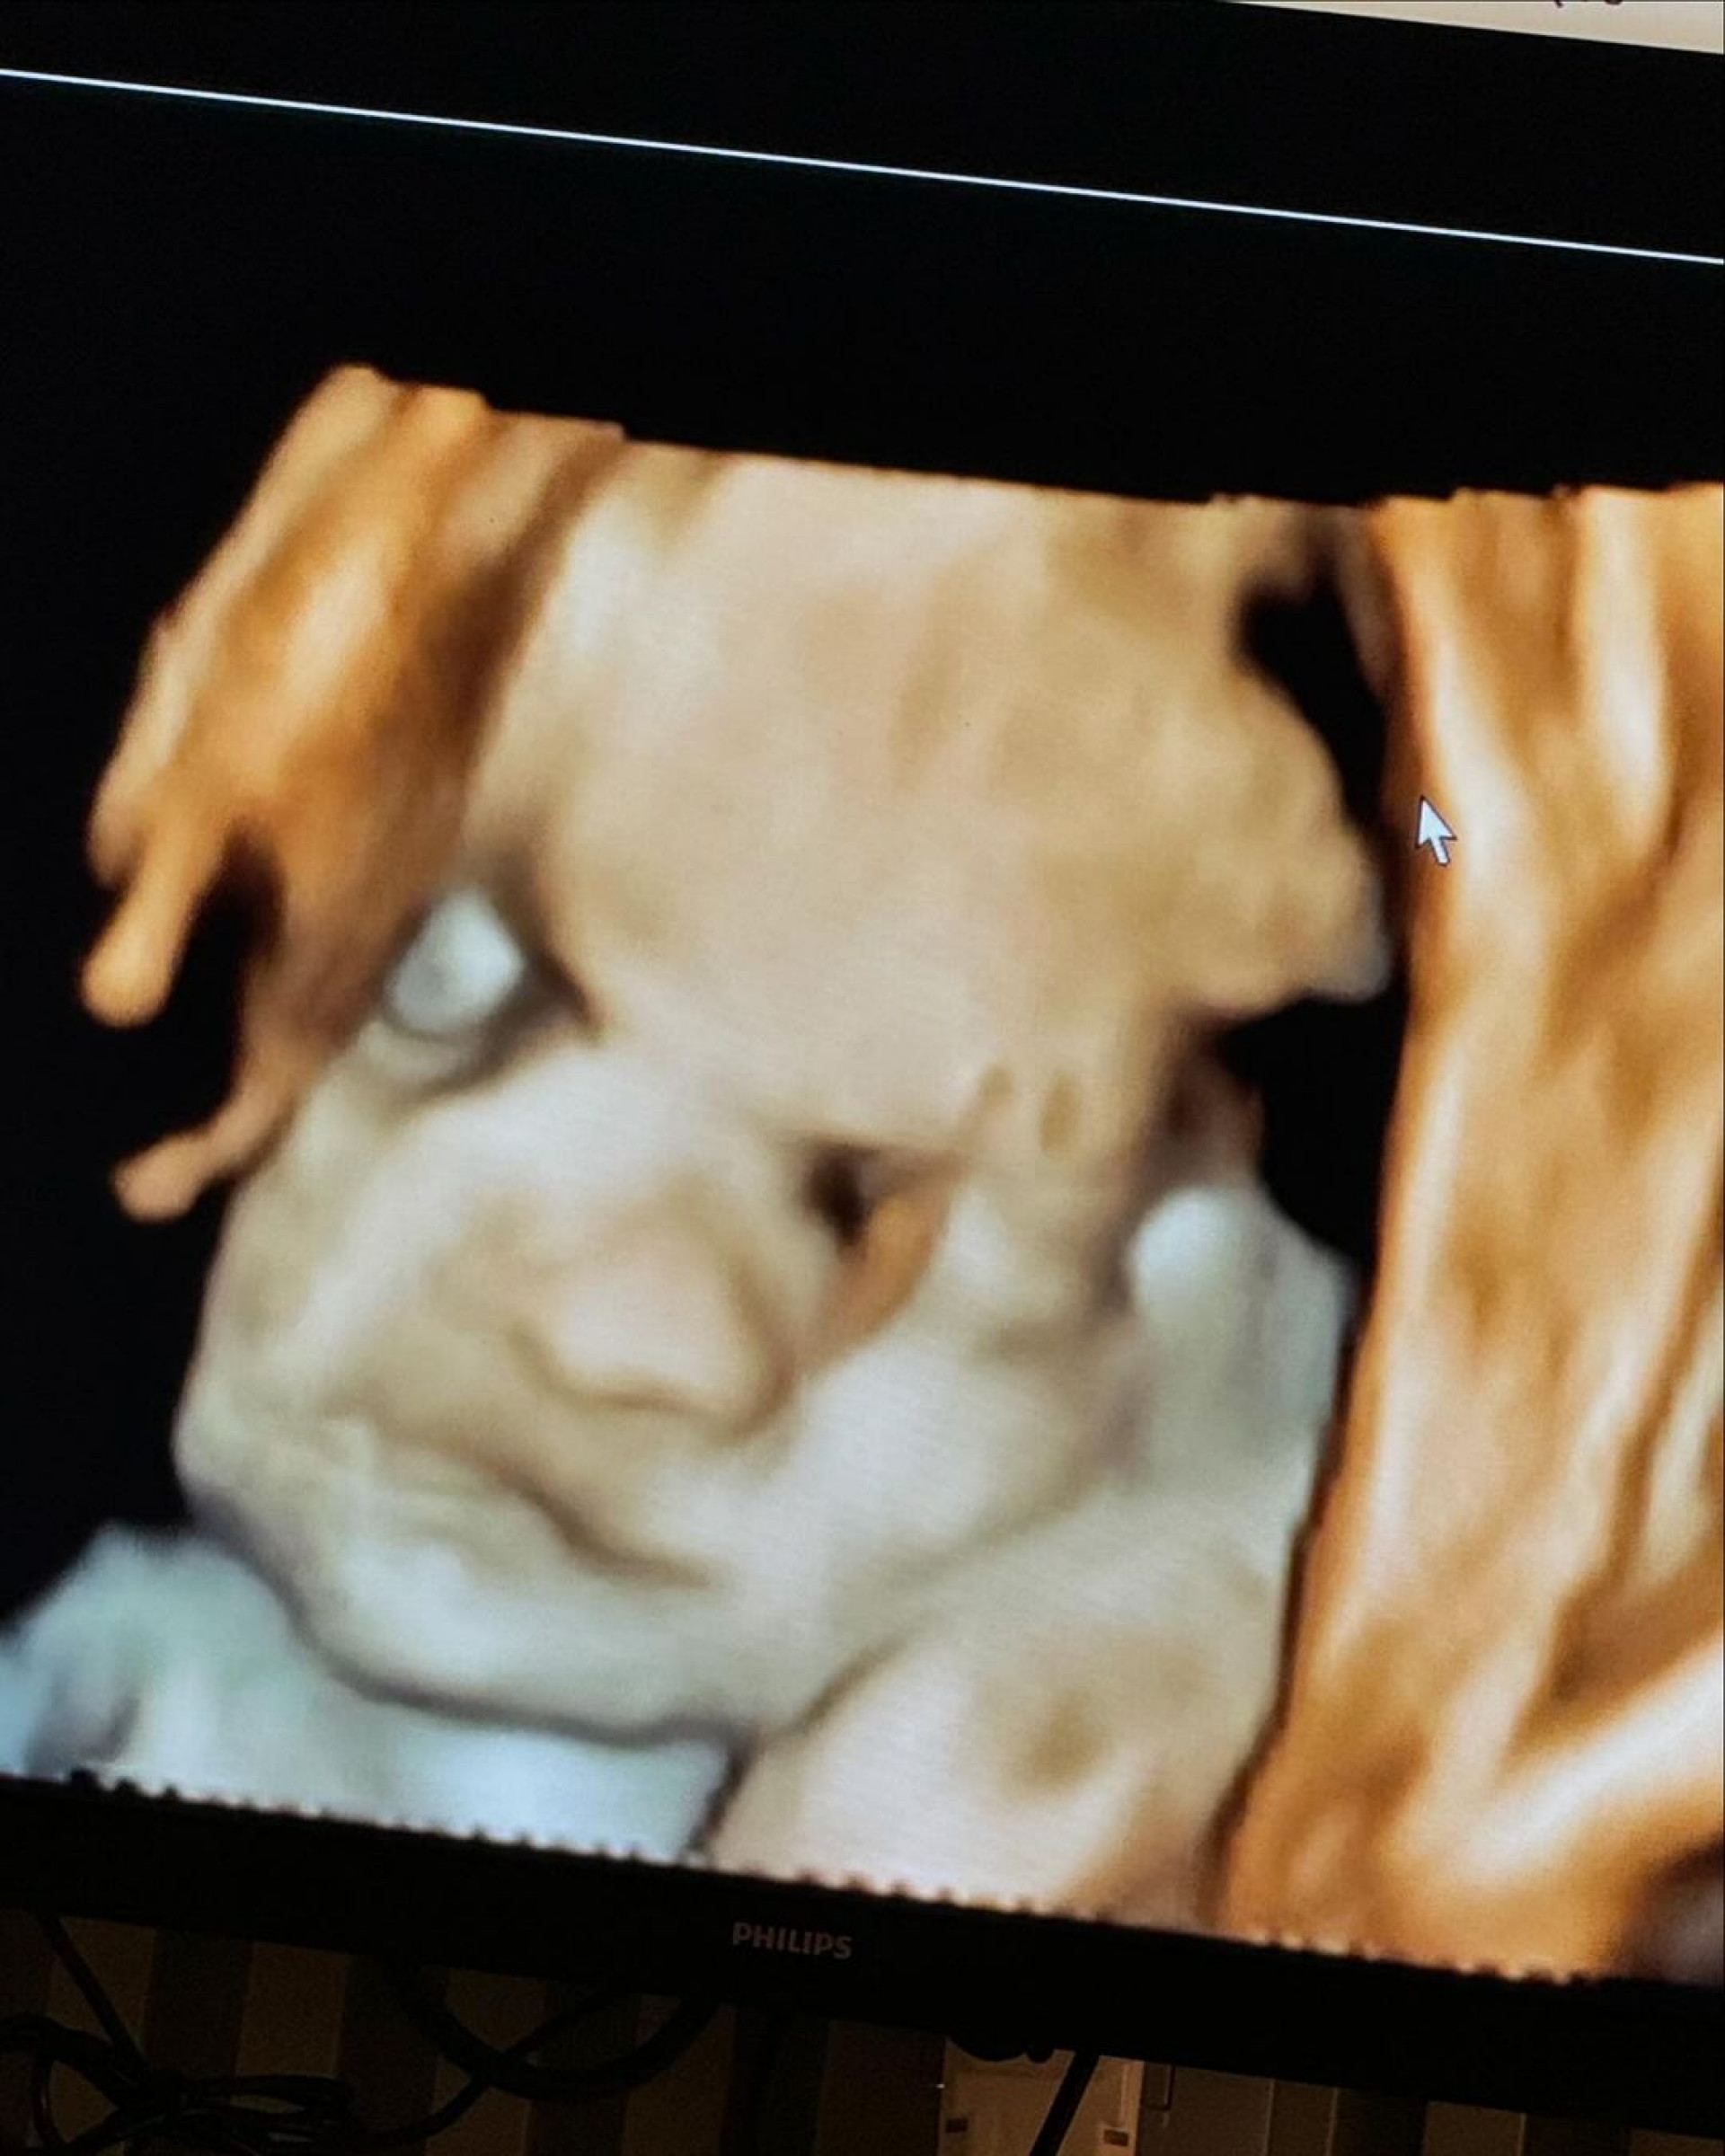

Virginia Fonseca mostra ultrassom do terceiro filhoReprodução

Rio - Grávida, Virginia Fonseca compartilhou, nesta sexta-feira (28), imagens do ultrassom de seu terceiro filho, José Leonardo, fruto de seu relacionamento com Zé Felipe. Em seu Instagram, a influenciadora falou sobre a expectativa da chegada do pequeno e revelou que tem o achado parecido com a filha, Maria Flor, de 1 ano.

"Meu Deus! Conseguimos ver um pouquinho do rostinho do Zé Leonardo. Eu estou achando ele a cara da Floflo (risos). Ô mãezinha, estou ficando ansiosa para te ver totoco. Que você venha com MUITA saúde e que Deus abençoe sua vida sempre, amém", escreveu na legenda da publicação.

Nos comentários, os internautas repercutiram a semelhança entre os filhos do casal, que também são pais de Maria Alice, de 2 anos. "Mas gente, a Maria Flor está ficando a cara da Maria Alice… Daqui a um tempo os três vão parecer muito", disse uma seguidora. "As imagens desses ultrassom são muito engraçadas, mas lembra a Floflo mesmo", afirmou outra. "Eu achei parecido um pouco com a Maria Alice", opinou uma fã.